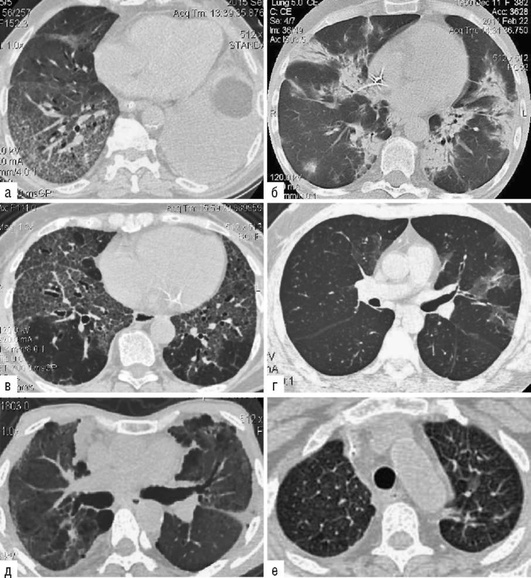

Лучевые методы исследования. Рентгенологическая картина при ЭТА зависит от стадии заболевания. В начальной фазе выявляются признаки отека интерстициальной ткани легких и распространенные мелкоочаговые затенения. При прогрессировании процесса формируются двусторонние изменения легочного рисунка по типу интерстициального фиброза, преимущественно в нижних отделах легких (рис. 2.28). В далеко зашедших случаях определяется мелко- и крупноячеистая деформация легочного рисунка. Описаны случаи, когда единственным рентгенологическим признаком болезни был односторонний плевральный выпот. Отсутствие каких-либо изменений на рентгенограммах отнюдь не исключает ЭТА. Так, при бериллиозе у 23-59% больных может выявляться умеренно выраженная двусторонняя лимфоаденопатия, а в ряде случаев - рентгенотрицательная форма бериллиоза (Dweik R.A., 2015). У 30% из 71 больных ЭТА, наблюдавшихся нами в клинике пульмонологии, в момент обследования изменений на рентгенограммах не было (Орлова Г.П., 2019). Группа больных ЭТА была обозначена условно как рентгенотрицательная группа. Уточнить диагноз помогает КТ легких, выявляющая интерстициальные изменения в легочной ткани по типу «матового стекла», усиление и деформацию легочного и сосудистого рисунка (рис. 2.29), фиброзные изменения тяжистого и звездчатого типов, на поздних стадиях - «сотовое легкое». ВРКТ выявляет «матовое стекло» и другие изменения в легочной паренхиме, которые не видны при обычном рентгенологическом исследовании. Но даже ВРКТ не всегда выявляет изменения в легочной ткани. Так, в 25% случаев гистологически подтвержденного хронического берил-лиоза легких ВРКТ была нормальной (Dweik R.A., 2013; Амосов В.И., Сперанская А.А., 2015; Amanullah S. et al., 2015).

Проведенное нами динамическое исследование КТ-паттернов у 42 больных ЭТА показало трансформацию отдельных типов интерстициальных пневмоний по мере прогрессирования патологического процесса в фиброзную НСИП или ОИП (рис. 2.30), что подтверждает объединительную концепцию интерстициальных пневмоний вне зависимости от этиологического фактора, которые являются не отдельными нозологическими формами, а стадиями течения фиброзирующего процесса в легких (Илькович М.М., Новикова Л.Н., 2018; Орлова Г.П. и др., 2019).